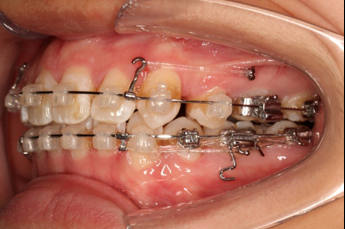

8.第17个月:2018.03.01 ◆ 上tpa加17/27牵引钩,压低;下颌43/32重粘,下颌0.016*25niti

9.第20个月:2018.5.25 ◆ 拆tpa,16/26粘tube上和0.14*25cu-niti 下颌0.018*25niti

2018.03.01上TPA加17、27颚侧牵引钩,压低17、27颚尖下颌43、32重粘,下颌0.016*25niti

2018.04.20  间隙基本关闭,上颌重新整平,精调

2018.5.25  (19个月)拆TPA,16、26粘tube 上颌0.14*25cu-niti  下颌0.018*25niti2018.7.23  上颌 0.017*25TMA,下颌0.017*25ss43压低曲,双侧后牙垂直牵引